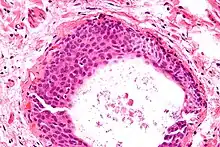

Micrograph of a Walthard cell nest, the entity Brenner tumours are thought to arise from. H&E stain.

Micrograph of a Walthard cell nest, the entity Brenner tumours are thought to arise from. H&E stain.